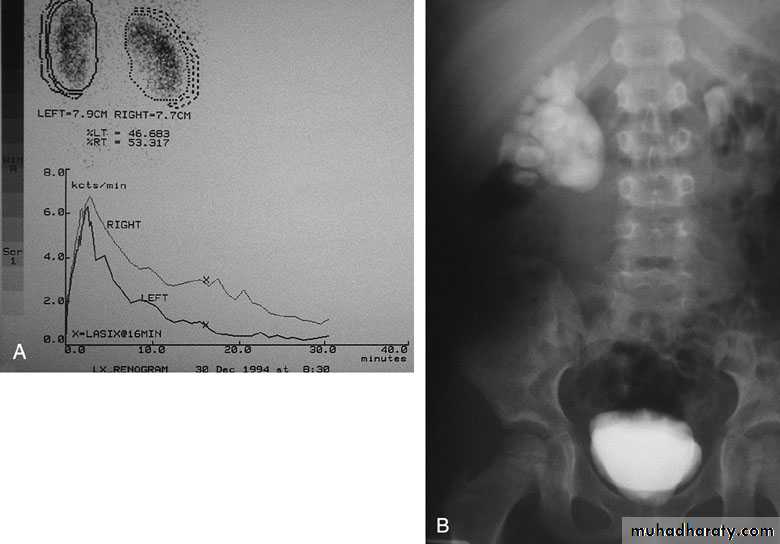

Radionuclide Renography: to see the

split function of each kidney

Pressure-Flow Studies: Whitaker test

IVU: diagnostic , hydronephrosis with

fixed stenotic segment or complete

obstruction